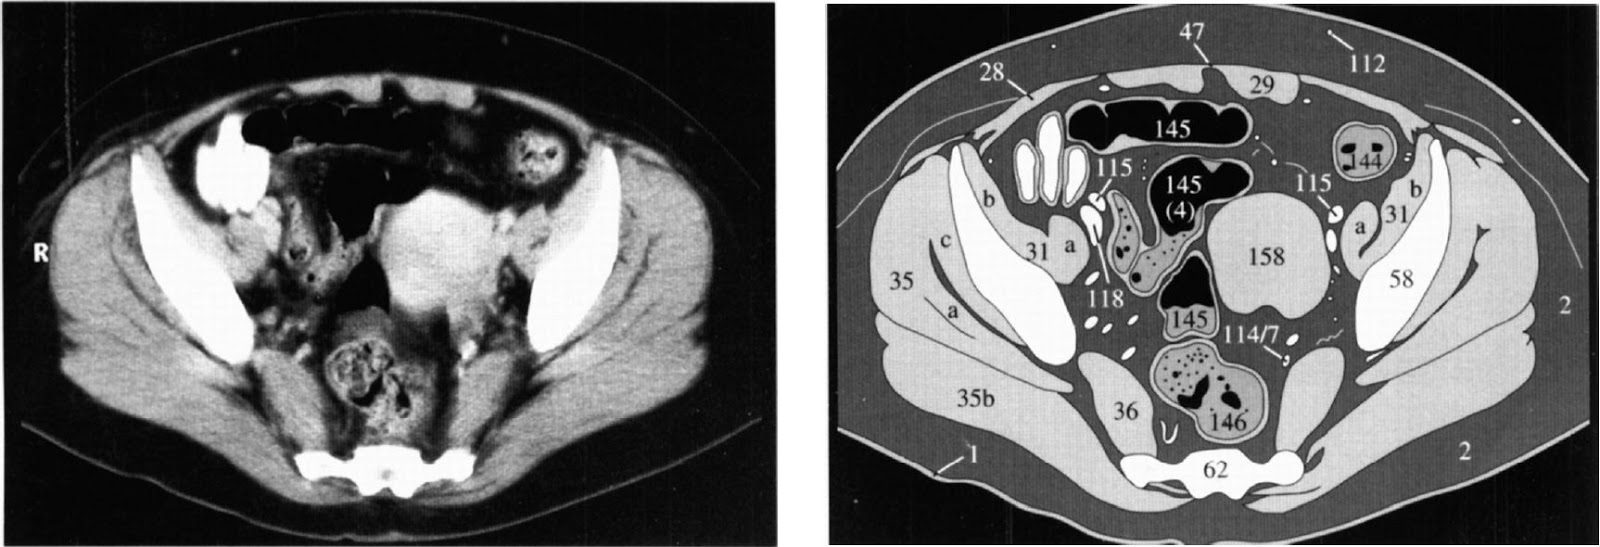

Ниже

представлены КТ-срезы и их схемы, которые необходимо использовать в качестве

эталонов при проведении сравнительного анализа органов брюшной полости (анатомия женского таза).

брюшной стенки: наружная косая (а), внутренняя косая (b), поперечная (c).

29. Прямая

31.

Повздошно-поясничная, поясничная (a), повздошная (b) мышцы.

35. Внутренняя

(a), большая (b) и малая (c) ягодичные мышцы.

58. Повздошная

кость.

112. Верхние

надчревные сосуды.

115. Наружная

повздошная артерия.

118. Наружная

повздошная вена.

145.

Сигмовидная кишка.

146. Прямая

кишка.

158. Матка.

160. Влагалище,

шейка матки.